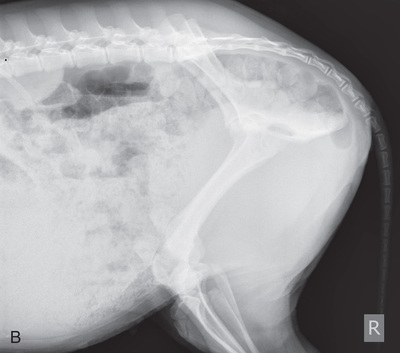

Pelvis, skull, spine, thorax, and abdomen radiographs are completed much like those in horses. In the case of a small calf, radiographs may be performed in the clinic with use of positioning and techniques similar to those used for a large dog. A mobile x-ray machine can be used to take thoracic or abdominal radiographs in a small calf (Fig. 24.62).

Small ruminant patients (sheep/goats) and swine can be radiographed much like small animals (Fig. 24.63). Because they can be easily transported, small ruminant patients are often radiographed within the clinic setting.